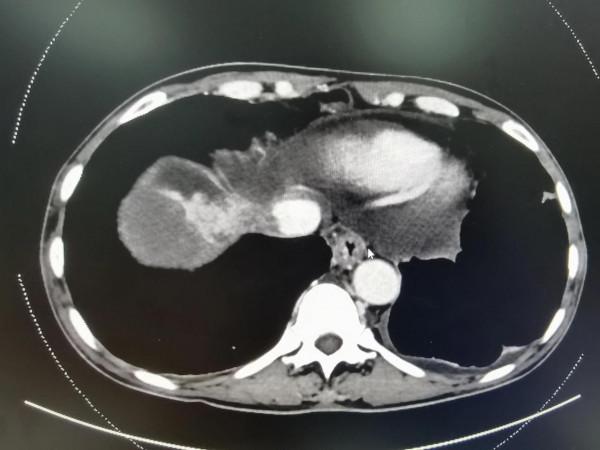

晚期肝癌的病人也不要輕易放棄!近2-3年,晚期肝癌的治療獲得了較大的突破,介入治療+靶向藥+PD1的治療組合,大部分情況下可以取得不錯的治療效果。這是一例非常晚期的肝癌病人,這要是在2-3年前,估計就是勸病人回家,該吃吃該喝喝,預計不會超過3個月的生存期。本例患者巨塊型肝癌合併下腔靜脈癌栓(下腔靜脈幾乎完全堵塞並臨近心房口了)及門靜脈主幹及右支癌栓的病人,經過2次的介入治療(肝動脈灌注化療術(HAIC)後,病灶明顯的縮小,癌栓明顯的消退,腫瘤指標直線下降,整個人的精神狀態持續好轉,未來可期。